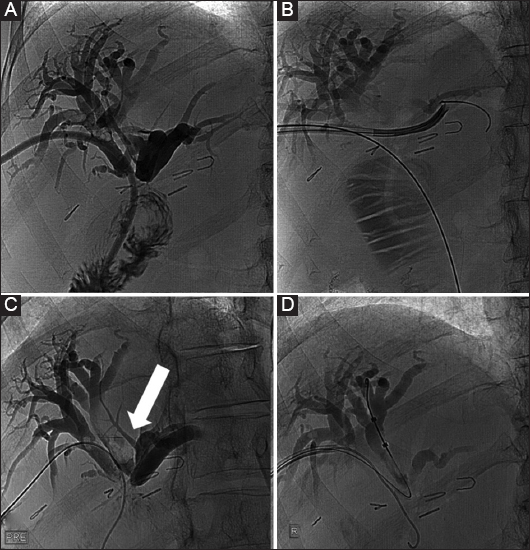

Figure 3 A 48-year-old female patient with benign stenosis post biliodigestive anastomosis. (A) Initial drainage because of multiple small stones. (B) Cholangioscopic inspection to assess the presence of stones that were not visible in the cholangiogram. (C) Three months later, a new cholangiogram revealed the presence of a large stone (arrow). (D) The stone was retrieved with an extraction balloon. Presence of a “buddy-wire” to maintain access to the biliary tree